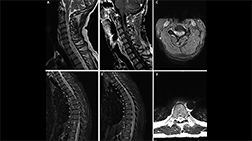

Longitudinally extensive enhancing optic nerve lesion in neuromyelitis optica spectrum disorder (NMOSD)

A. Axial T1 fat-saturated post-gadolinium MRI in a patient with AQP4+ NMOSD demonstrates bilateral optic neuritis over more than 50% of the optic nerves (arrows).

B. Optical coherence tomography taken 1 year after bilateral optic neuritis demonstrates thinning of the right and left retinal nerve fiber layers (right 62 μm, left 54 μm; normal thickness on OCT is more than 80 μm; OCT images contributed by Dr. Sara Qureshi).